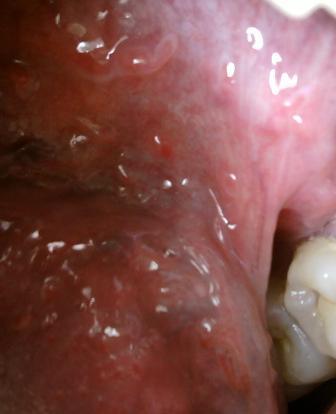

使用公共马桶会感染尖锐湿疣病毒吗现在就一起和石家庄九洲皮肤病医院专家一起来了解一些有关尖锐湿疣的常识,以便于当身体有异常的时候,可以更好的应对。尖锐湿疣是人类乳头瘤病毒,并且该病毒一般会通过直接接触传染,间接接触传染和母婴传染而患病,尖锐湿疣病原体唯一宿主就是人类,因此建议大家应该引起重视,平时生湖中也应该注意避免感染病毒而患病,大家在和患者接触的时候应该谨慎,平时多加注意。远离病毒集中区域:

使用公共马桶会感染尖锐湿疣病毒吗夜店,Ktv,,公用坐便等等是病毒集中区域,因此建议大家在平时应该引起重视,以免不慎感染病毒而患病。以上就是石家庄九洲皮肤病医院专家的观点,希望可以帮助到您,如有任何不理解的情随时拨打石家庄性病医院九洲康复热线:66560637这里有专家24小时为您答疑解惑。在这里预祝广大患者朋友们可以早日康复,远离病痛的折磨。